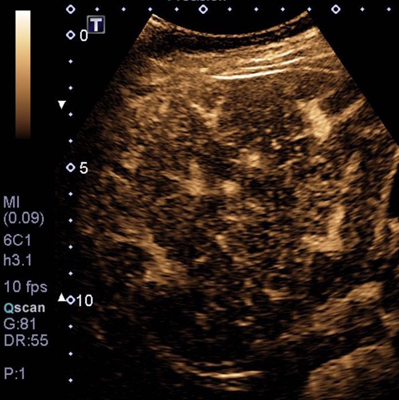

A l’aide d’un produit de contraste spécifique (Sonovue ®) constitué de microbulles très réfléchissantes aux ultrasons ; il est possible d’imager la vascularisation sanguine des organes à des fins diagnostiques, en échographie.

Cet examen fournit une analyse en temps réel de la vascularisation des organes abdominaux, en particulier le foie et les reins.

Il permet dans certains cas précis de caractériser des lésions, d’affiner le diagnostic ou de compléter un dossier pour lequel un doute subsiste.